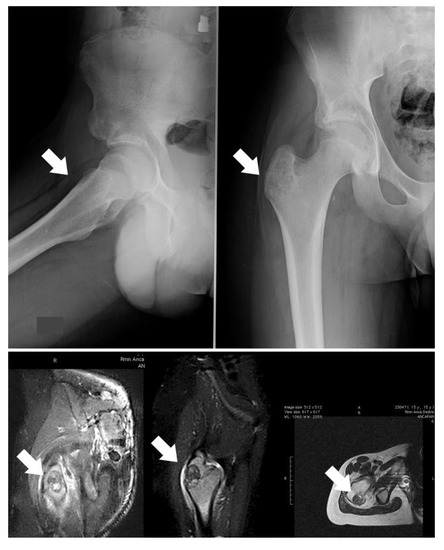

The gold-standard treatment for OBL is surgery; generally, intralesional surgery is suggested for grade 2 lesions (Figure 1A), whereas wide resection is more indicated for grade 3, more aggressive tumors or for lesions located in areas where a possible local recurrence could be difficult to treat (Figure 1B). Indeed, the site of onset also has to be assessed; a more aggressive lesion could be treated intralesionally if located in the distal femur, while lesions located in the spine or pelvis are more suitable for resection even if they do not have an aggressive appearance.

The most frequent site is the vertebral column (28–36%), mainly the posterior elements and pedicles (Figure 1B) [18]. OBL surgery plays an important role in the spine: the vicinity of the dura and nerve roots limits the application of thermoablation techniques although, with improved expertise, minimally invasive technique are gaining more space also in this complex localization.

Figure 1. (A) Twenty-two-year-old male patient affected by stage 2 distal humerus OBL (white arrows): the lesion was considered suitable for intralesional surgery; (B) twenty-one-year-old male patient affected by a D3 left pedicle OBL (white arrows): wide resection was performed to decrease the risk of local recurrence.